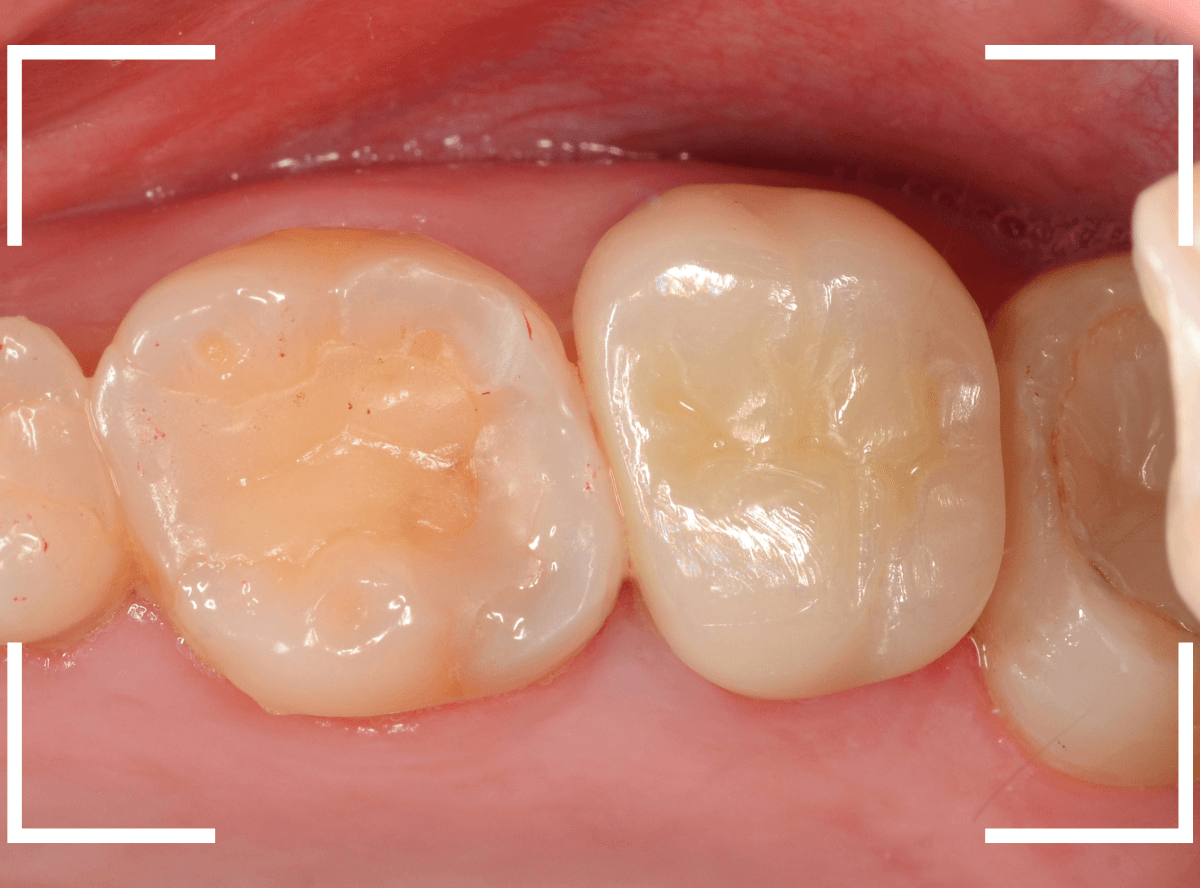

Case.20 メタル・インレーとメタル・クラウンをジルコニアにやり替え

「下の奥歯の銀歯を白くしたい」というご希望の患者さんです。

メタル・インレーとメタル・クラウンが入っていますね。

set後の写真です。

患者さんにも満足していただける仕上がりになりました。

(2024年11月)

治療前後の写真になります。

やはり、印象が大きく変わりますね。